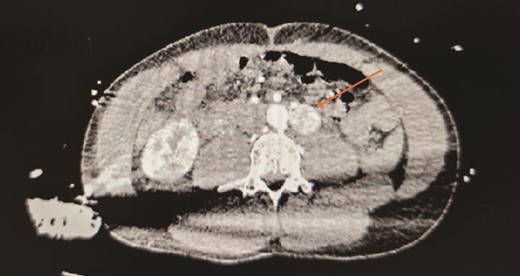

He underwent a robotic excision of his paraganglioma in a right lateral position, using a transperitoneal approach with three robotic ports and one assistant port in the midline. The left colon was mobilized medially, exposing the tumour. After identifying the ureter and gonads, the tumour was dissected freely using a vessel sealer, before removing it in a specimen bag. Operation was uneventful (Figs 3 and 4).

Well circumscribed mass with extensive vascularisation is located and isolated, with no surrounding tissue necrosis or invasion observed. Real time video footage revealed a pulsatile mass.